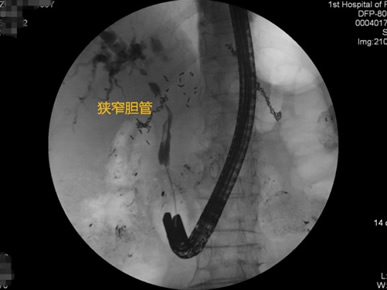

胃毕-Ⅱ术后乳头倒置 胃毕-Ⅱ术后胰管胆管双支架植入 胃毕-Ⅱ术后金属支架植入

胃毕-Ⅱ术后肝门部胆管狭窄 胃毕-Ⅱ术后金属支架植入